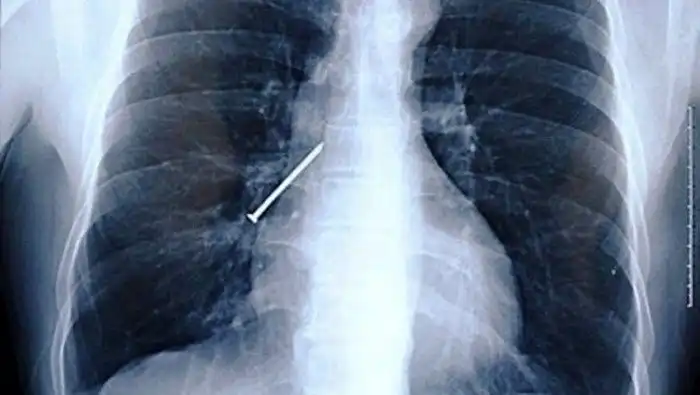

Забитые крылышки

Не до шуток было жителю Британии, которой перекусил в кафе и обнаружил в курином крылышке гвоздь. Он незамедлительно обратился за медицинской помощью, и выяснилось, что еще один гвоздь мужчина успел проглотить. К счастью, все обошлось без последствий.

И снова гвозди

Видимо, картошку и гвозди как-то притягивает друг к другу. Эту жуть обнаружила 11-летняя школьница из Техаса в своей картошке фри. Ребенка спасла внимательность. А история получила в обществе большой резонанс.

Запеченный гвоздь

Так и до перелома челюсти недалеко.